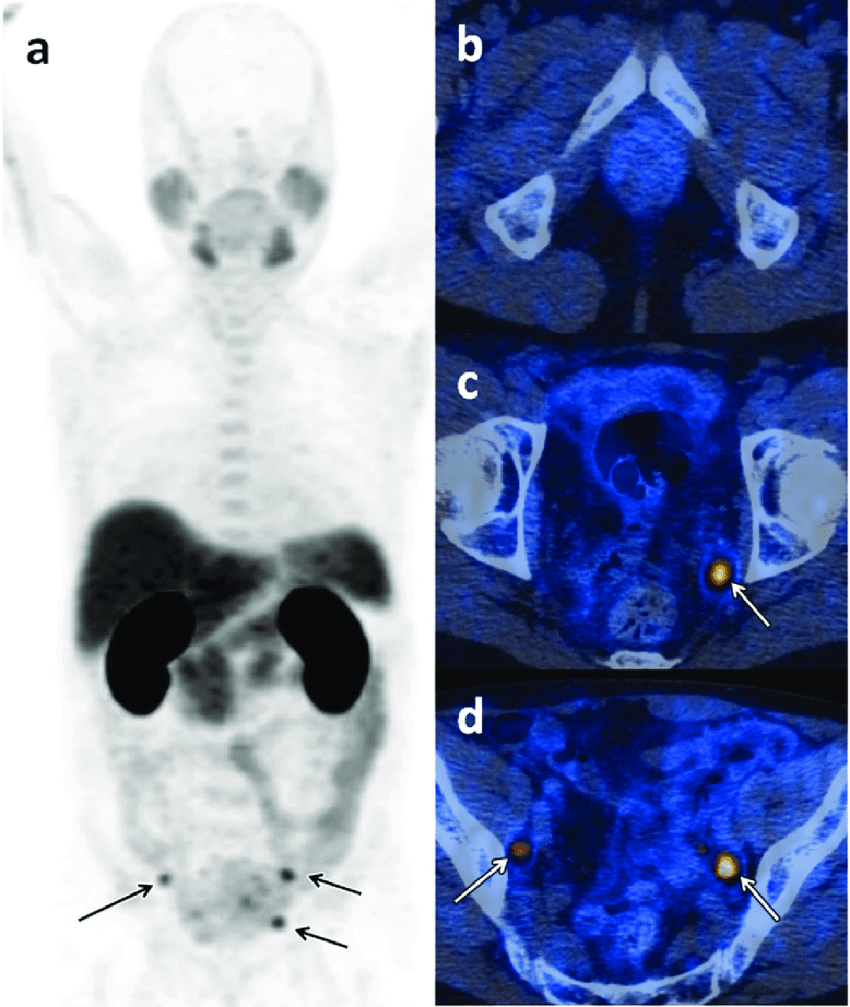

In addition to oncology, 18F-Choline PET/CT is increasingly used to identify parathyroid adenomas in patients with hyperparathyroidism. This becomes especially valuable when ultrasound or sestamibi scans are inconclusive.

By accurately locating small or ectopic adenomas, 18F-Choline PET/CT assists surgeons in planning focused and minimally invasive procedures, thereby improving surgical outcomes.